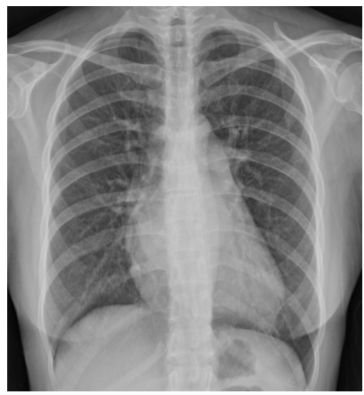

15. 50歲男性,患有糖尿病,胰臟癌及恐慌症,因突發性呼吸困難至急診求診。病患並無明顯胸痛或冒冷汗,意識清楚但情緒緊張,理學檢查發現體溫36.5℃,血壓 145/95 mmHg,脈博112/min節律規則, 呼吸 24/min快且深;四肢冰冷有輕微發紺現象。頸靜脈壓12 cm H2O,無明顯心雜音。呼吸音雙側正常,腹部平坦無壓痛,四肢活動正常亦無水腫。護理人員給予脈衝血氧定量計 (pulse oximeter) 偵測發現SpO2 84%,急診醫師隨即指示使用Venturi mask O2 35%。約半小時後,病人自覺症狀略為減緩,此時之動脈氣體分析: PH 7.50, PaO2 70mmHg, PaCO2 25 mmHg, HCO3 23 mEq/L, one touch blood glucose 320 mg/dl. EKG除竇性頻脈外其餘正常,胸部Ⅹ光如附圖,下列診斷何者最有可能? (A) Acute pulmonary embolism (B) Panic disorder related hyperventilation syndrome (C) Diabetic ketoacidosis (D) Endobronchial foreign body (E) Bronchial asthma